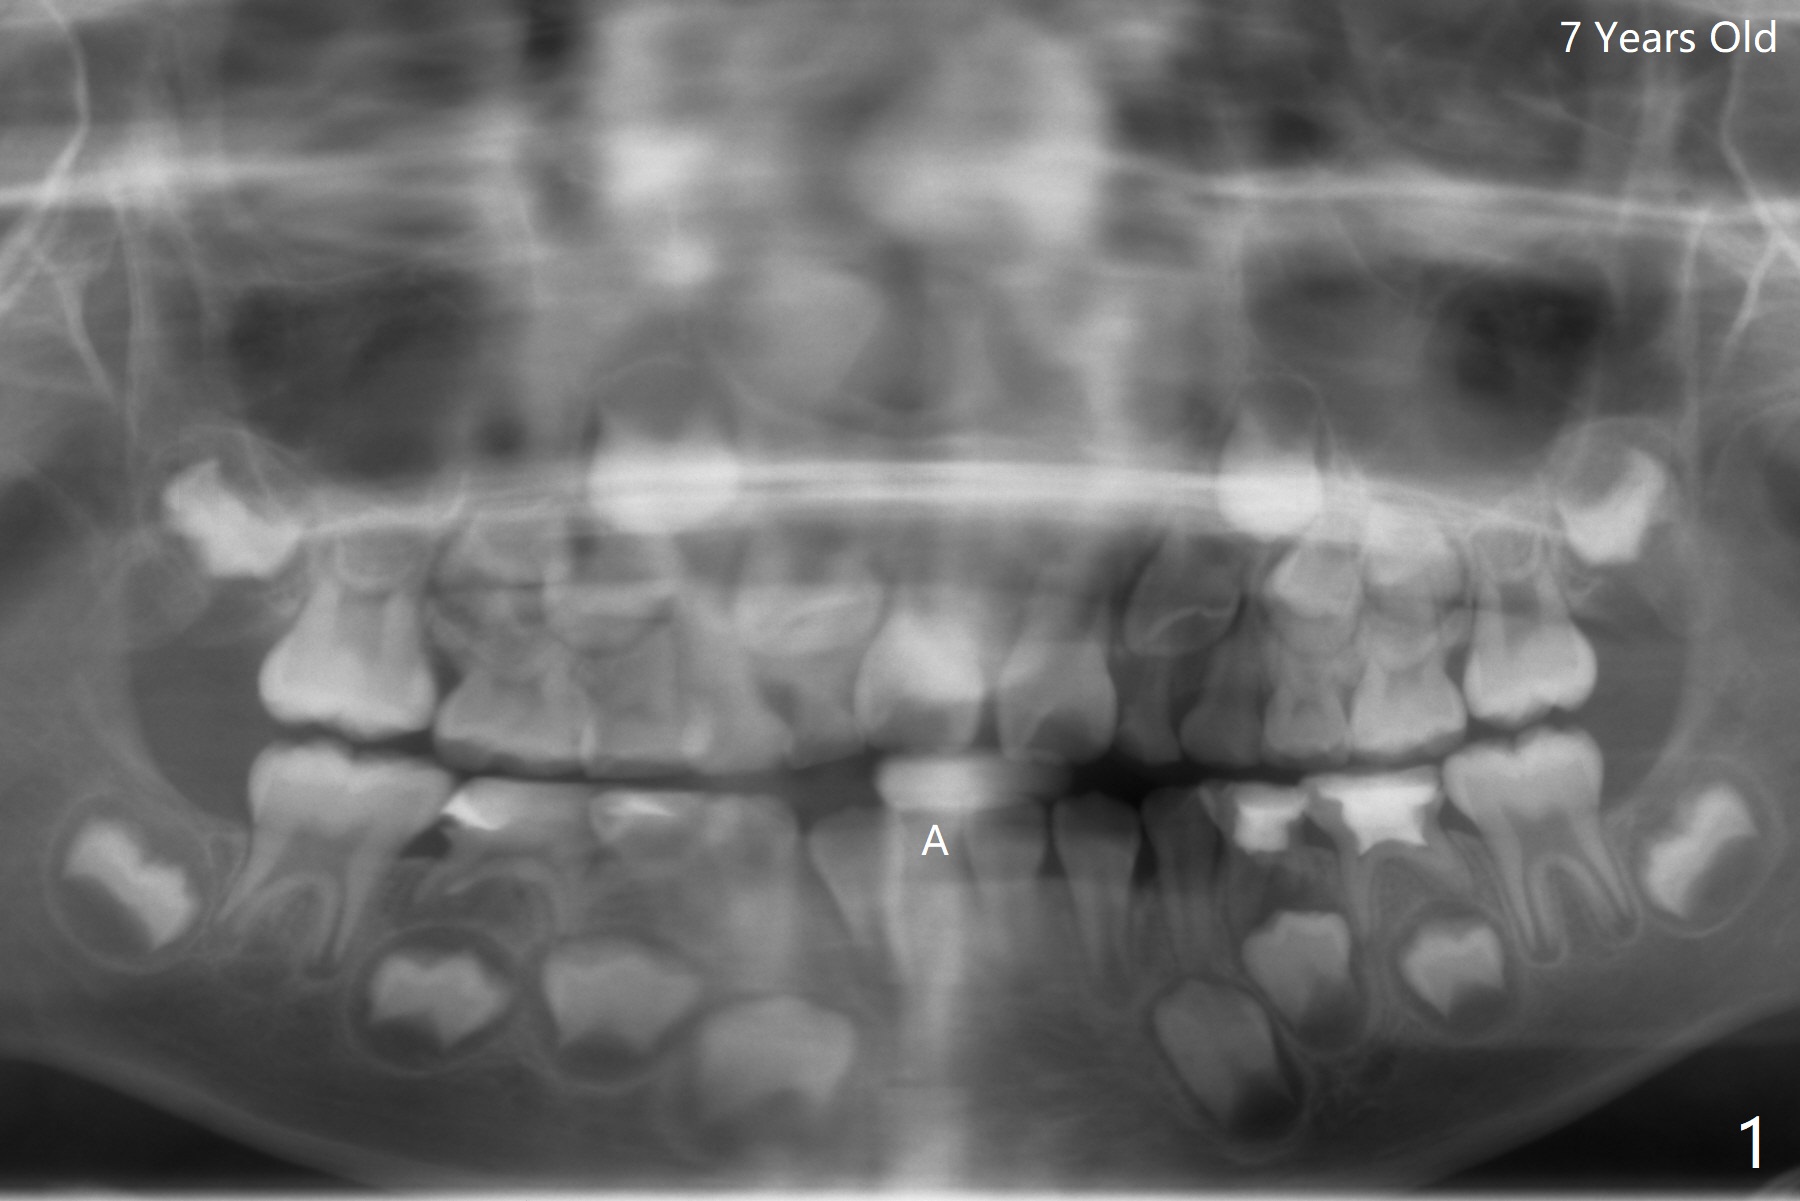

A 7-year-old woman has congenital missing lower right central incisor (Fig.1). At age of 13, she requests extraction of the displaced and discolored deciduous central incisor (Fig.2,3 A). After extraction, self drifting may alleviate crowding and anterior overjet and closes the space? Perfect solution, extract the A followed by driftodontics...fixed appliances as needed. Dr. Shaughness 12/25/2019